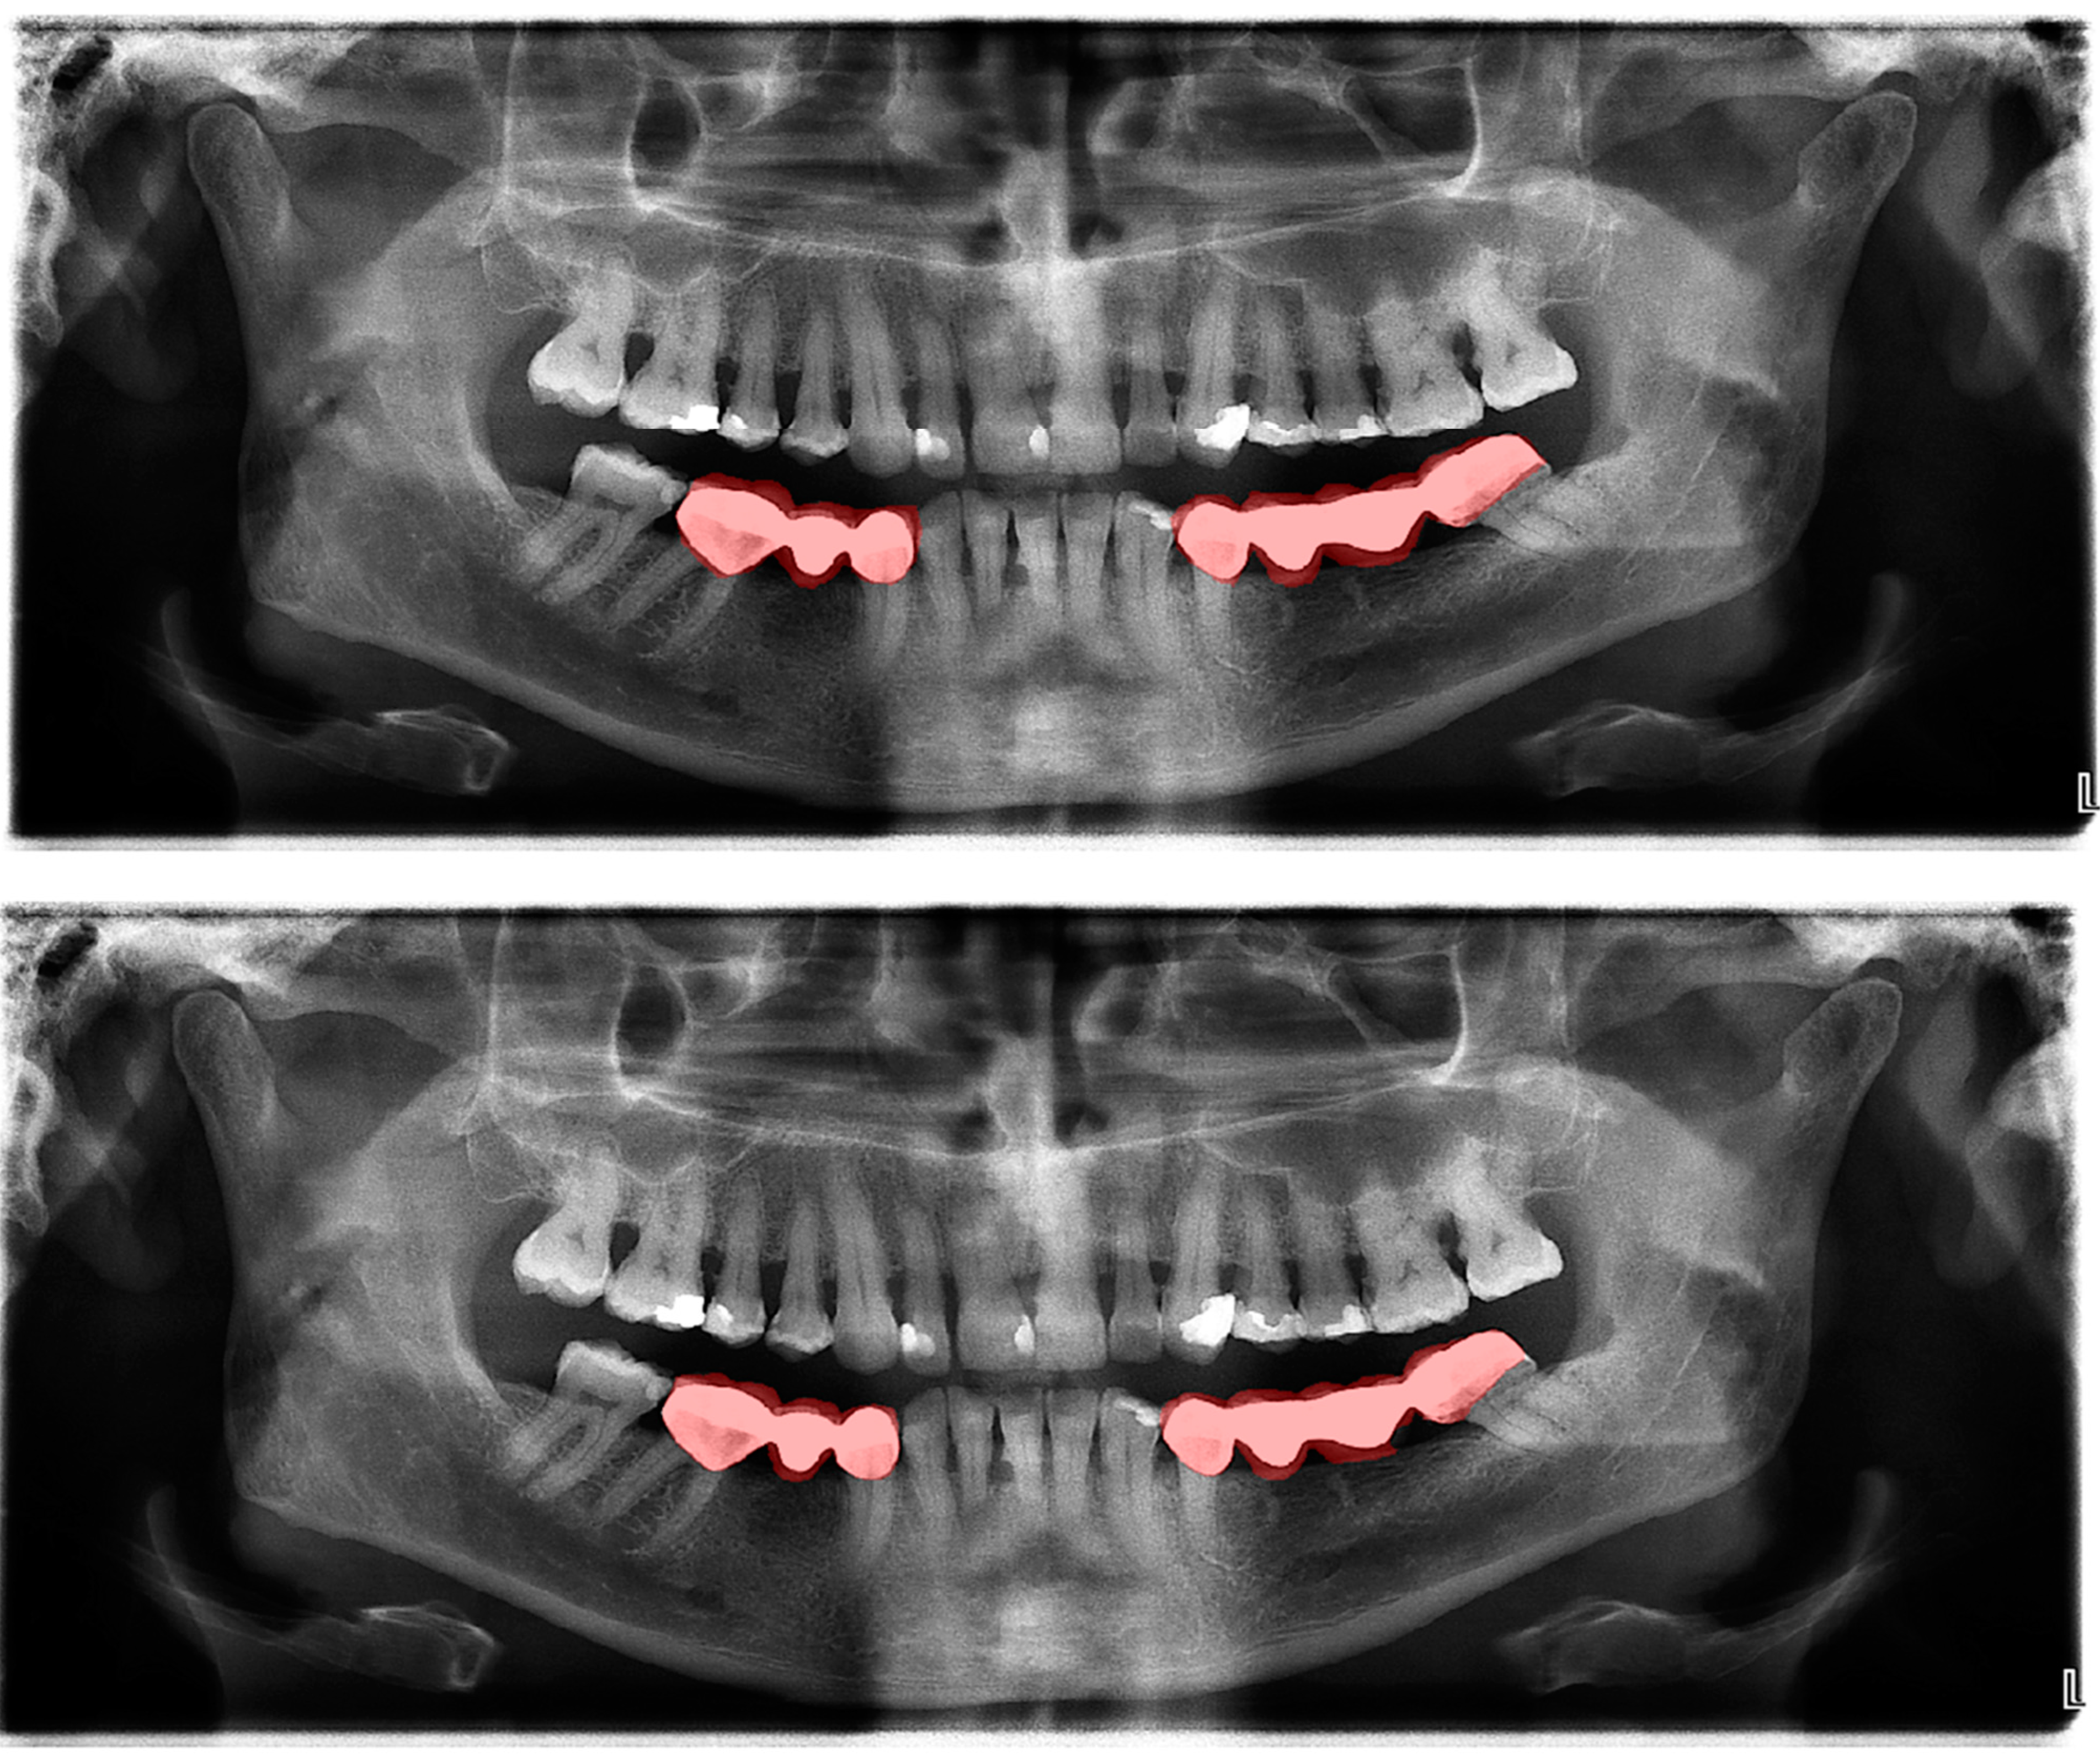

Figure 4.

Automatic segmentation of the bridges. Manual segmentation (upper image) and automatic segmentation (lower image) can be seen above.